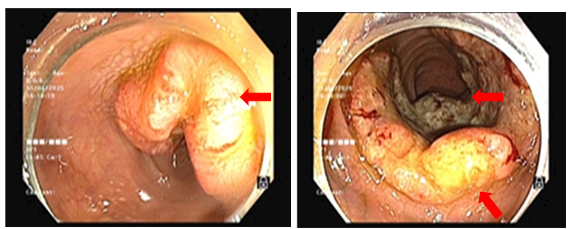

- Nội soi đại trực tràng (06/2025): Trực tràng: Cách rìa hậu môn ~ 1 cm có khối sùi loét chiếm 4/5 chu vi trực tràng. Cách rìa hậu môn ~ 10 cm có sùi loét chiếm 3/4 chu vi trực tràng. Niêm mạc trực tràng còn lại có vài polyp kích thước ~ 0.2 – 0.5 cm

Hình 3: Tổn thương tại 2 vị trí trực tràng: Cách rìa hậu môn ~ 1 cm có khối sùi loét chiếm 4/5 chu vi trực tràng. Cách rìa hậu môn ~ 10 cm có sùi loét chiếm 3/ 4 chu vi trực tràng.